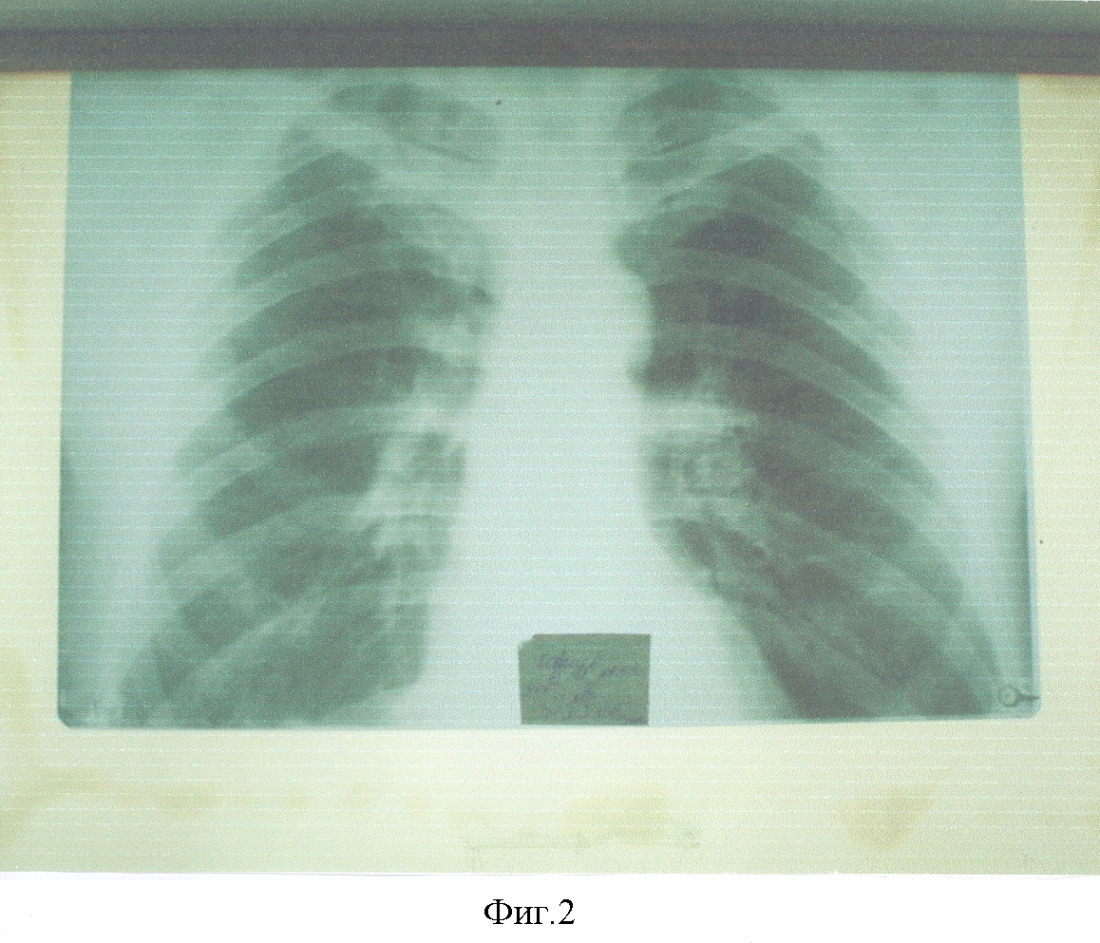

Больной К., 50 лет, ист. бол. №22640Ф направлен в РНИОИ в ноябре 2005 г. Цимлянским ПТД после безуспешного лечения туберкулеза правого легкого в течение 3-х лет. При поступлении жаловался на боли в грудной клетке, слабость, потливость, похудание, одышку при физической нагрузке. Из анамнеза выяснено, что заболевание началось с повышения температуры тела до 38°С с апреля 2002 г. После флюорографического обследования поставлен диагноз очаговоинфильтративный туберкулез верхней доли правого легкого. В течение года лечился в противотуберкулезном диспансере. Затем в течение 2-х лет находился под диспансерным наблюдением фтизиатра. В августе-сентябре 2005 г. в связи с прогрессированием заболевания повторно лечился в противотуберкулезном диспансере. В связи с отсутствием положительного эффекта от лечения, ухудшением общего состояния, появлением боли в грудной клетке, одышки, слабости, потливости, похудания самостоятельно обратился в РНИОИ, был госпитализирован в отделении торакальной пластической хирургии (см. фиг.1).

Фиг.1. Больной К-в. Обзорная рентгенограмма до начала лечения.

Где с ноября 2005 г. по февраль 2006 г. проведено 3 курса АГХТ с интервалом между курсами – 1 месяц, по вышеописанной методике. Суммарно за 3 курса получил цисплатина – 600 мг; доксорубицина – 40 мг, циклофосфана – 6000 мг. Уже после I курса отмечена полная регрессия клинических симптомов, а к концу III-го курса почти полное рассасывание патологического очага в правом легком, подтвержденном рентгенологически (см. фиг.2 и 3).

Фиг.2. Больной К-в. Обзорная рентгенограмма после проведения трех курсов АГХТ.